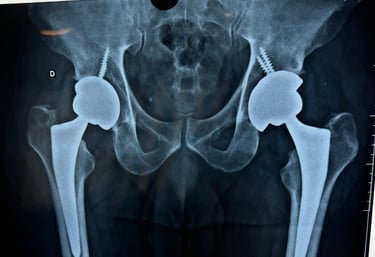

Especialização em Cirurgia de Quadril - Hospital de Base de São José do Rio Preto (SP)/FAMERP